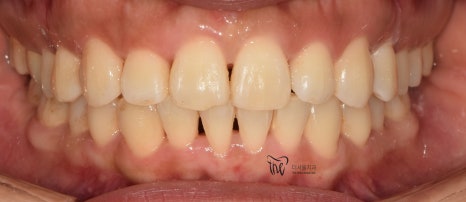

일단 초진 사진을 먼저 보여드리겠습니다.

이 분은, 부정교합 2급 인데도 돌출입의 정도가

그리 심하지는 않습니다.

심미선을 기준으로, 입술이 살짝 걸리는데

이 정도라면 비발치로도 진행이 가능한 부분입니다.

다만, 앞니들이 앞쪽으로 많이 뻐드러져

있기 때문에 입술의 긴장감이 많이 형성이

되어있는지라 이 부분은, 치아 재 배열을

통해서 충분히 개선이 가능할것으로 보여집니다.

정면에서 봤을 땐, 불규칙한 총생들이 관찰되며

곳곳에 치석이 쌓여있는 것을 볼 수 있습니다.

측면에서 봤을 땐, 앞니들의 뻐드러짐과

불규칙한 치열을 동시에 관찰을 할 수 있습니다.